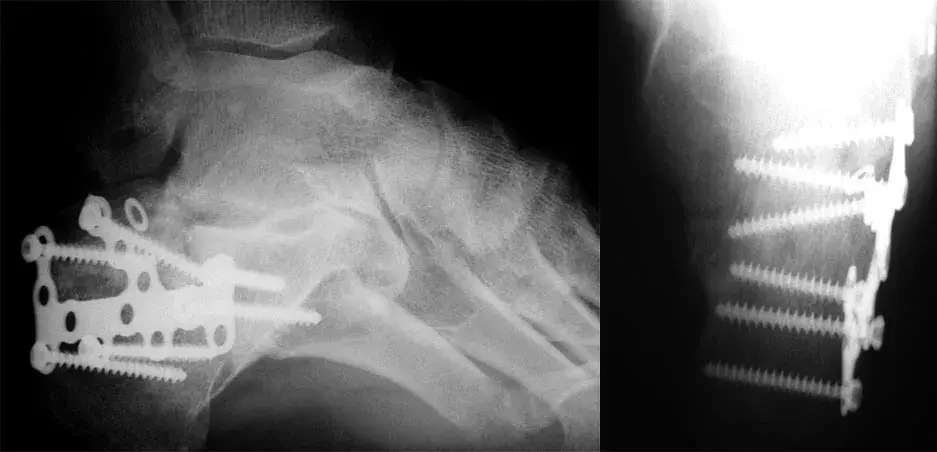

Celé odvětví technologie nese jméno svého objevitele. Rentgenové snímky zlomeniny patní kosti s plátováním.